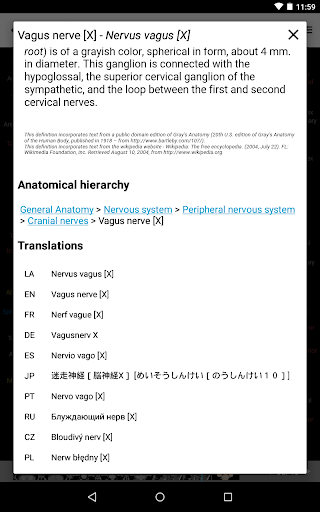

e-Anatomy tiene más de 26 000 imágenes que contienen series de imágenes en vistas axiales, coronales y sagitales, así como radiografías, angiografías, imágenes de disección, gráficos anatómicos e ilustraciones. Todas las imágenes médicas fueron etiquetadas cuidadosamente, más de 967 000 etiquetas disponibles en 12 idiomas, incluida la Terminologia Anatomica latina.

- Cambie de idioma con solo tocar un botón